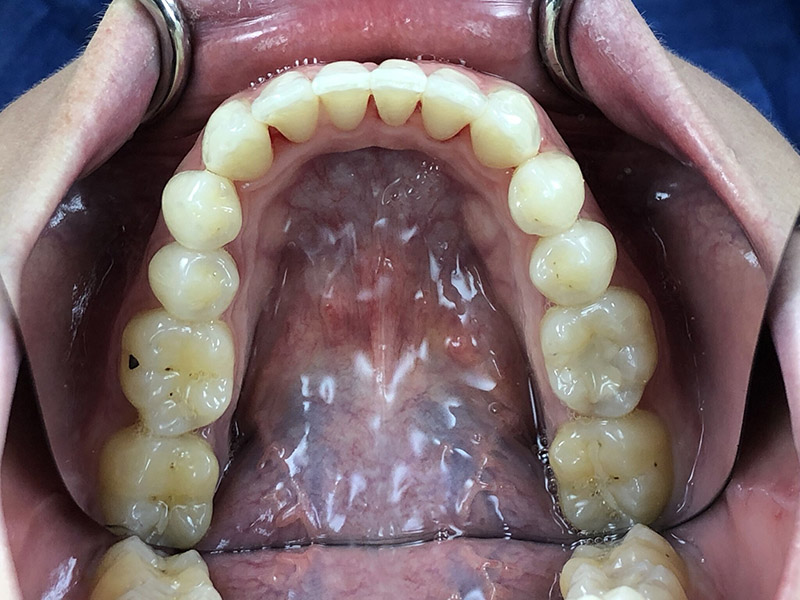

Un premier Clincheck fut réalisé, permettant de voir l’alignement souhaité et repositionner les dents selon le désir de la patiente.

On peut ici constater :

• Une série de 14 aligneurs

• Une série de réduction inter proximale maxillaire (RIP) pour un total de 1,5mm réparti entre les 15 et 25

• Une série de réduction inter proximale mandibulaire (RIP) pour un total de 0,9mm réparti entre les 15 et 25

• Des taquets répartis sur toutes les dents maxillaires pour optimiser les mouvements voulus

• Des taquets sur quelques dents maxillaires

Durée du traitement : 28 semaines, avec un changement des aligneurs toutes les 2 semaines.

Au bout du port de celles-ci, nous avons constaté un défaut dans le positionnement des dents, probablement dû à la difficulté de certains mouvements de tipping et un manque d’alignement des milieux.

Il a été décidé de réaliser une série de finitions supplémentaires pour parfaire le résultat.